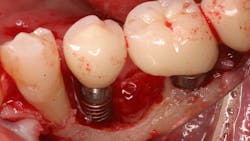

Once again, the literature is replete with case reports and case series describing soft- and hard-tissue loss due to excess dental cement left at the time of implant crown insertion.8 In one study, 90% of the implant crowns inserted with cement exhibiting inflammation and bleeding upon probing were due to cement in the peri-implant sulcus.9 Cement acts as a nidus for bacteria and induces a rapid hard-tissue loss around the dental implant fixture (figures 2 and 3).